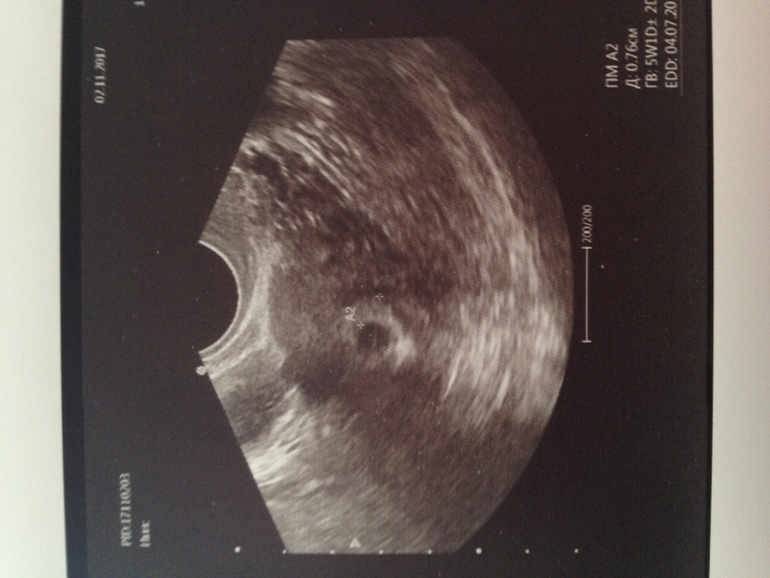

УЗИ в 5 недель

Вопросы про УЗИ, обследования и анализы: что, где, как, когда?Наше первое узи в 5 недель.Призналась доктору,что сама назначила себе лечение,из-за мазни,думала,она ругаться будет на меня,но она сказала,что можно увеличить прием до 3-х раз Дюфастона,и убрать Папаверин.По узи:сначала долго изучала,потом стала озвучивать)),я уже начала дергаться от её молчания...Все по сроку,единственное:сердцебиенияещё нет,сказала что маленький ещё,эмбриончика она не видит ,но плодное яйцо показала,рекомендовала придти в 7-8 недель послушать сердечко,и уже становиться на учёт ...Так и сделаю,что мне лишний раз ходить к своему гинекологу?на учёт все равно пока не поставят,да и не хотелось бы,чтобы копались лишний раз...Девочки,а в какой срок у ваших эмбриончиков стали прослушиваться сердечки? Наше первое фото)))

Была на УЗИ по менструации 5.3 срок пя 11 мм жт 3.5 эмбрион и сб не видно, срок поставили 5 недель )

У меня в 5 нед тоже было ПЯ и все. Через неделю пришла уже был эмбрион и сб.. теперь через 2 еще пойду сб послушать (8 нед) потом на учет и в 12 на скрининг)